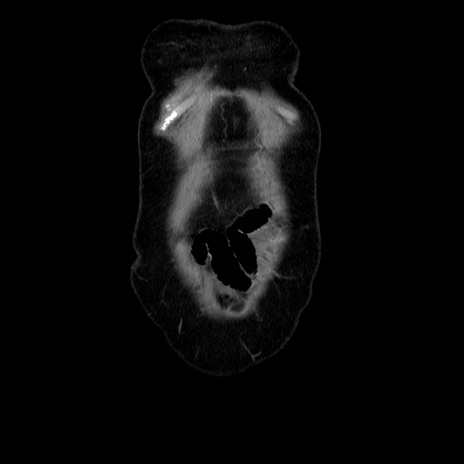

横断像